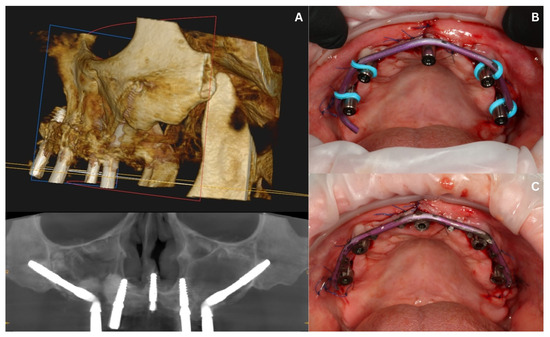

3.3. Surgery in the Maxilla and Immediate Loading—Stage II